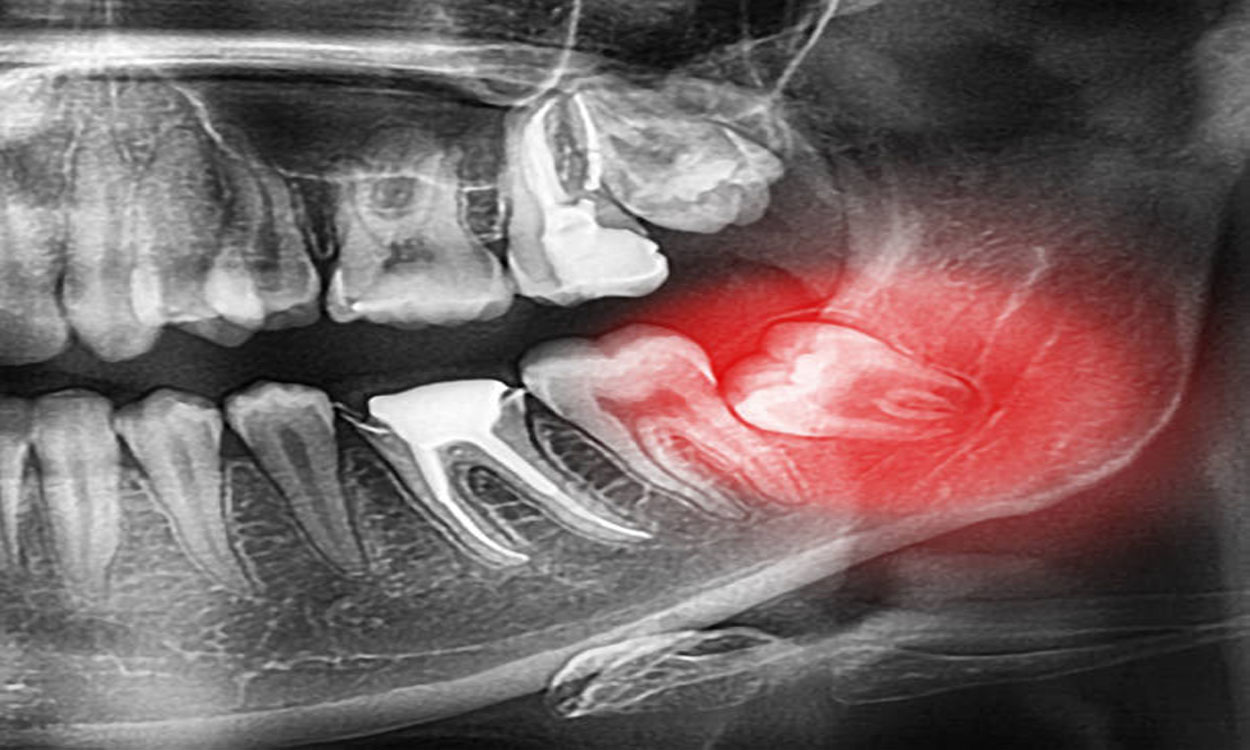

Çene Cerrahisi, ağız içerisinde yer alan yumuşak ve sert dokuların patolojilerinin tedavi edildiği bilim dalıdır. Çene Cerrahisi diş çekimi, gömülü diş ameliyatları, çene ve çevre dokularının kistlerinin tedavisi, çene tümörleri ve tedavileri, protetik cerrahi, çene yüz bölgesi ağrıları, çene eklem bozukluklarının tedavisi, tükürük bezi hastalıklarının teşhis ve tedavisi gibi yaklaşımları kapsamaktadır.

Önce cerrahi müdahale yapılacak hastadan klinikte gerekli filmler alınarak radyolojik incelemeler yapılır. Daha sonra hastaya yapılacak işlem ile ilgili ve işlemden sonra yaşayacakları ile ilgili bilgiler verilir. Bu bilgiler tamamen tahminlerden ibaret olup, işlemin ne kadar süreceği dikiş atılıp atılmayacağı, atılacaksa kaç dikiş atılacağı gibi sorular işlem sırasında belirlenmektedir.